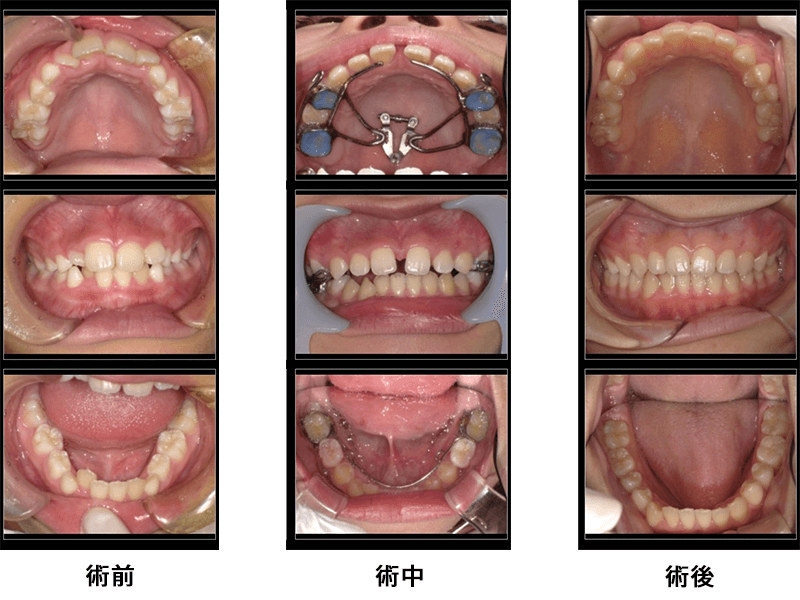

女性9歳

治療内容:顎顔面矯正

金額:440,000円

来院理由:歯並びといびき相談

施術の副作用(リスク):

前歯が一時的に開くことがあります。話しにくい、咬みにくい、飲みこみにくいなどの症状を生じることがあります。